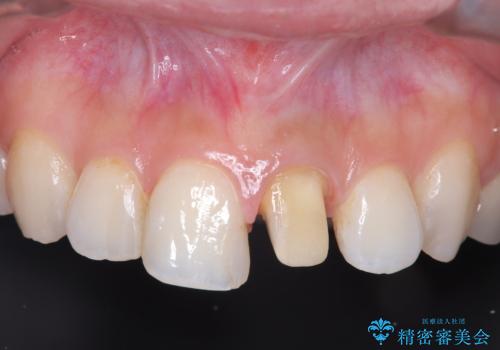

- 「前歯の色が気になる」を主訴に来院された患者様です。

前歯にプラスチックの材料が入っており、形と色が悪くなっていました。

失活歯だったため全体的に歯の色が暗くなっていました。